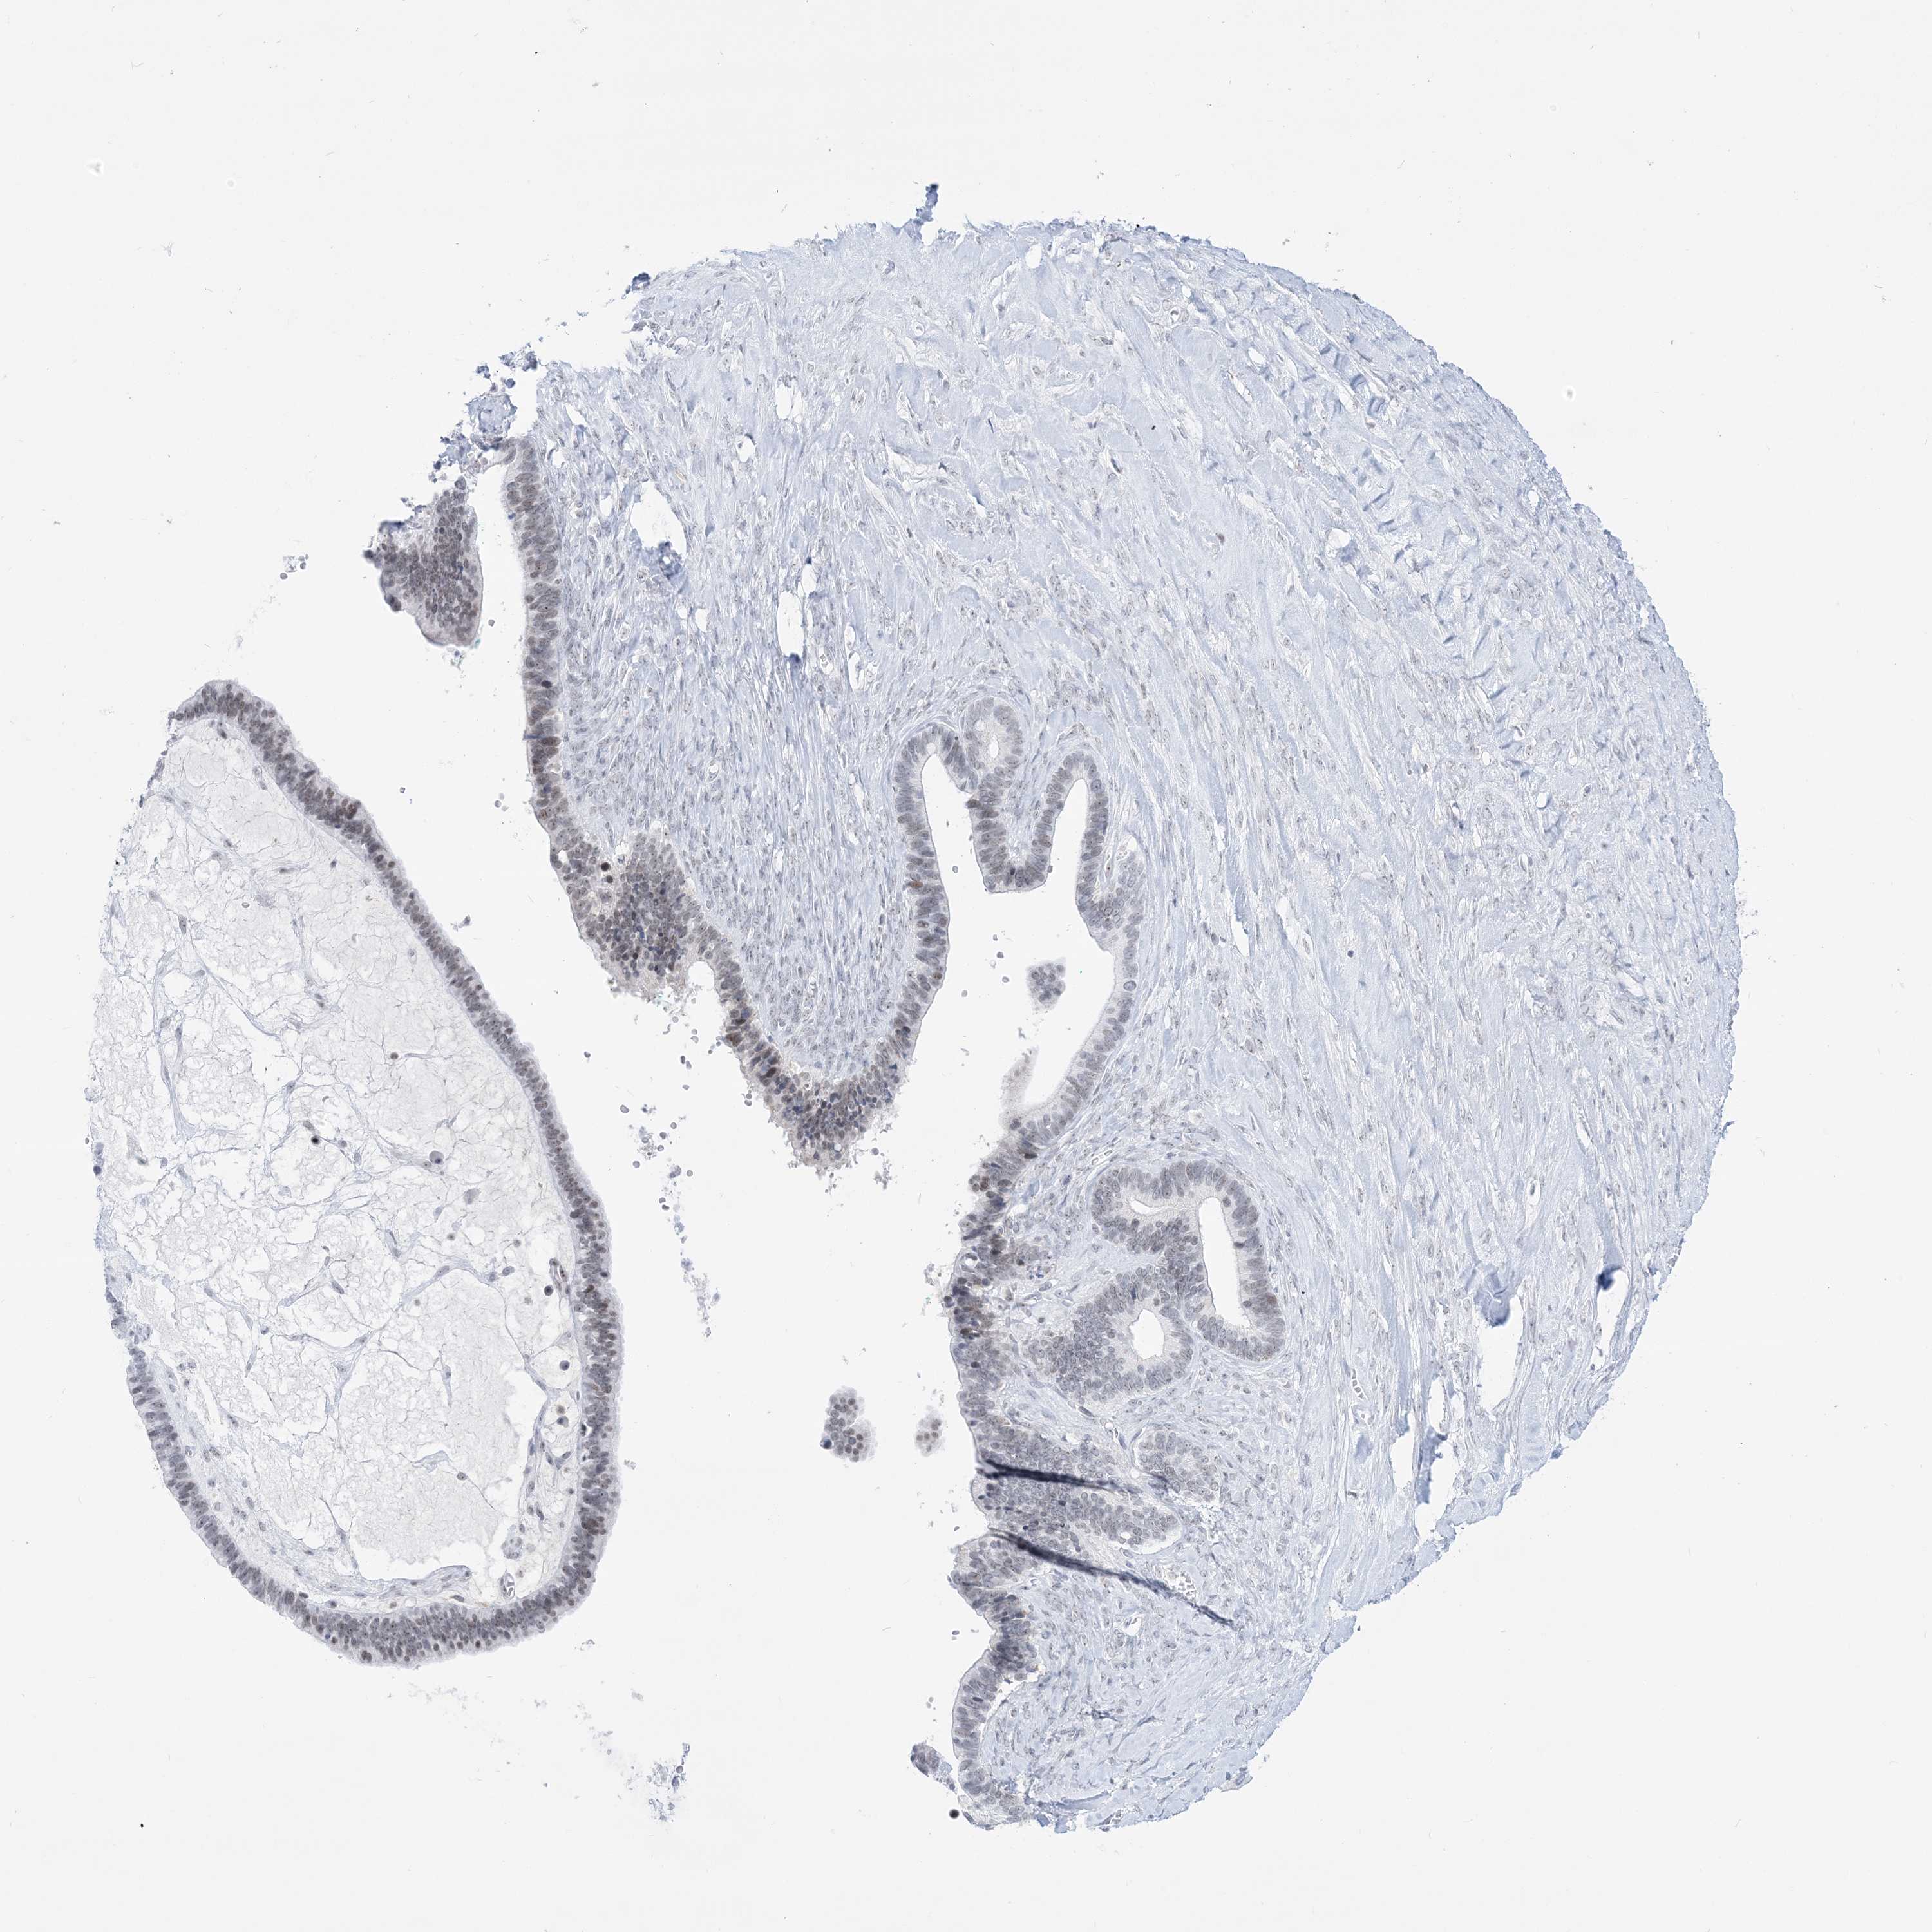

OVARIAN CANCER - Protein expressioni

A mouse-over function shows sample information and annotation data. Click on an image to view it in a full screen mode. Samples can be filtered based on level of antibody staining by selecting one or several of the following categories: high, medium, low and not detected. The assay and annotation is described here.

Note that samples used for immunohistochemistry by the Human Protein Atlas do not correspond to samples in the TCGA dataset.

Antibody stainingi

Antibody staining in the annotated cell types in the current human tissue is reported as not detected, low, medium, or high, based on conventional immunohistochemistry profiling in selected tissues. This score is based on the combination of the staining intensity and fraction of stained cells.

Each image is clickable and will lead to virtual microscopy that enables deeper exploration of all samples and also displays staining intensity scores, fraction scores and subcellular localization as well as patient and tissue information for each sample.

Antibody HPA036592

Antibody HPA036593

Cystadenocarcinoma, serous, NOS

Carcinoma, endometroid

Cystadenocarcinoma, mucinous, NOS

Carcinoma, NOS